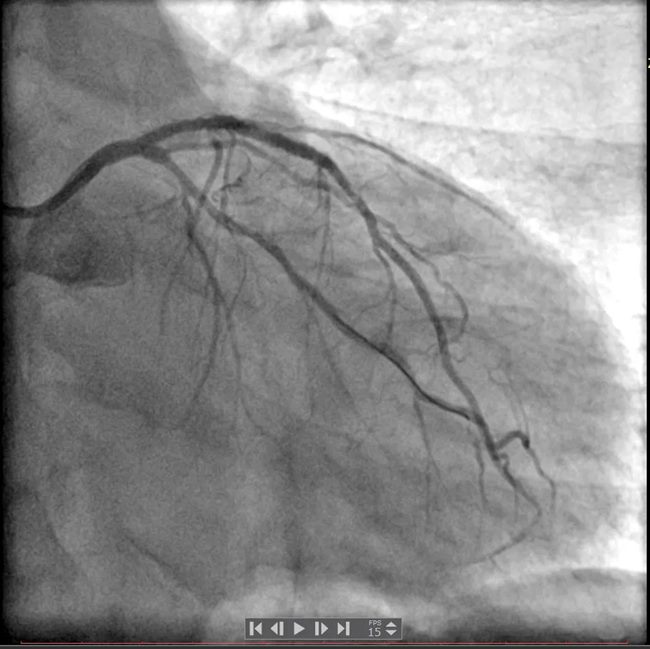

冠脉造影结果显示:左主干未见明显异常,前降支近中段可见支架影,近段支架内狭窄50%,前向血流TIMI3级;回旋支近段次全闭塞,前向血流TIMI2-3级;右冠中段弥漫性狭窄,最重处狭窄95%,前向血流TIMI3级。

最终由手术医师为买买提做了介入治疗:右冠置入支架1枚,回旋支置入药物球囊1枚。